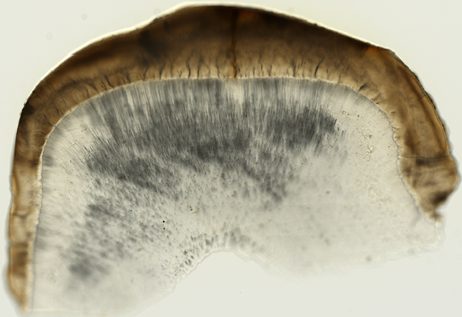

Oral Histology Slides

You may take a glance at the example photos of the available 36 slide below.

You may also download a complete list of oral histology slides for detailed information.